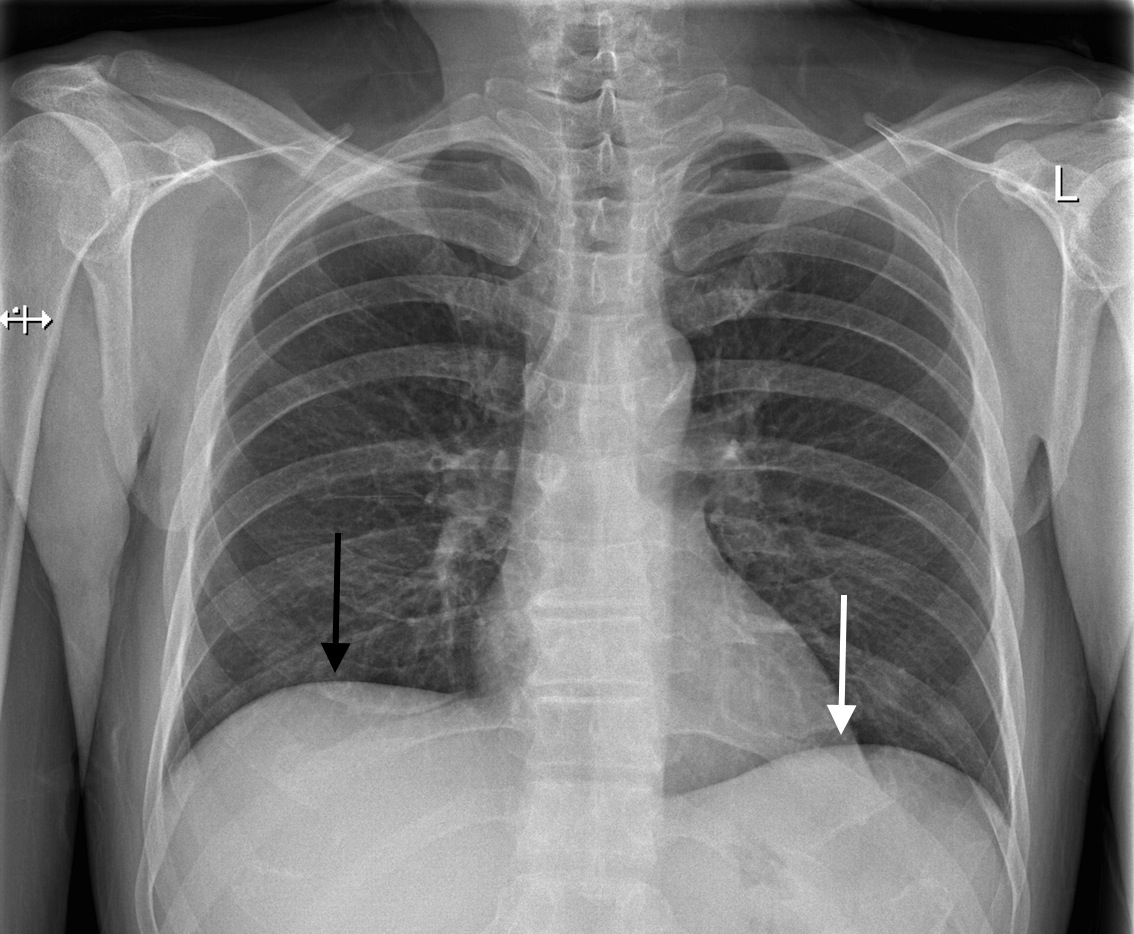

The spinal column is the body's main upright support. Thoracic Cage | Radiology Key